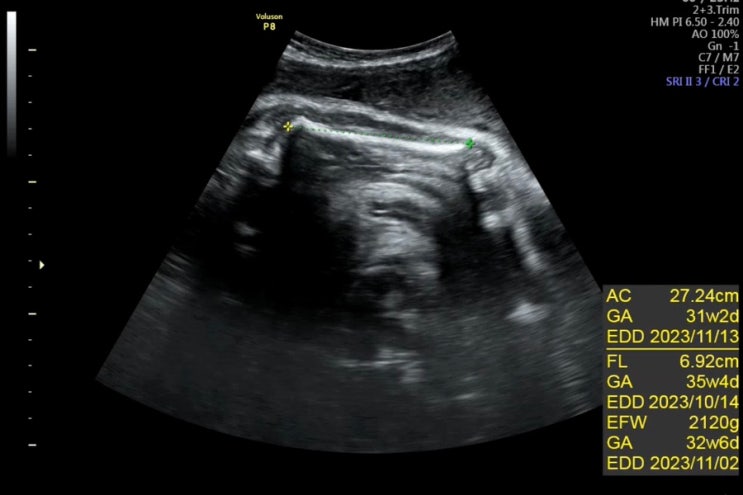

35주차 | 9개월 임산부 | 경산맘 | 경부길이짧음 | 폐성숙주사 | 분만 전 검사

10일이 지나 정기검진을 다녀왔어요. 35주가 되니 확실히 배 뭉침은 그전보다 잦아요. 하지만 자세를 바꿔...